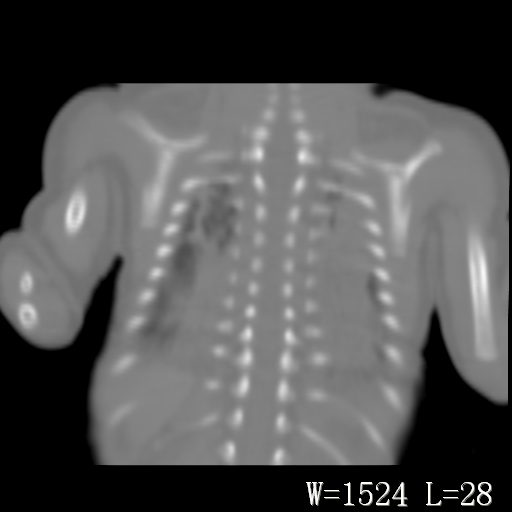

以下是引用改行者在2010-7-8 22:13:00的发言:[br]两肺野透光度降低伴细颗粒状影,两肺下叶见实变影,其内见支气管充气征。 多考虑新生儿肺透明膜病。